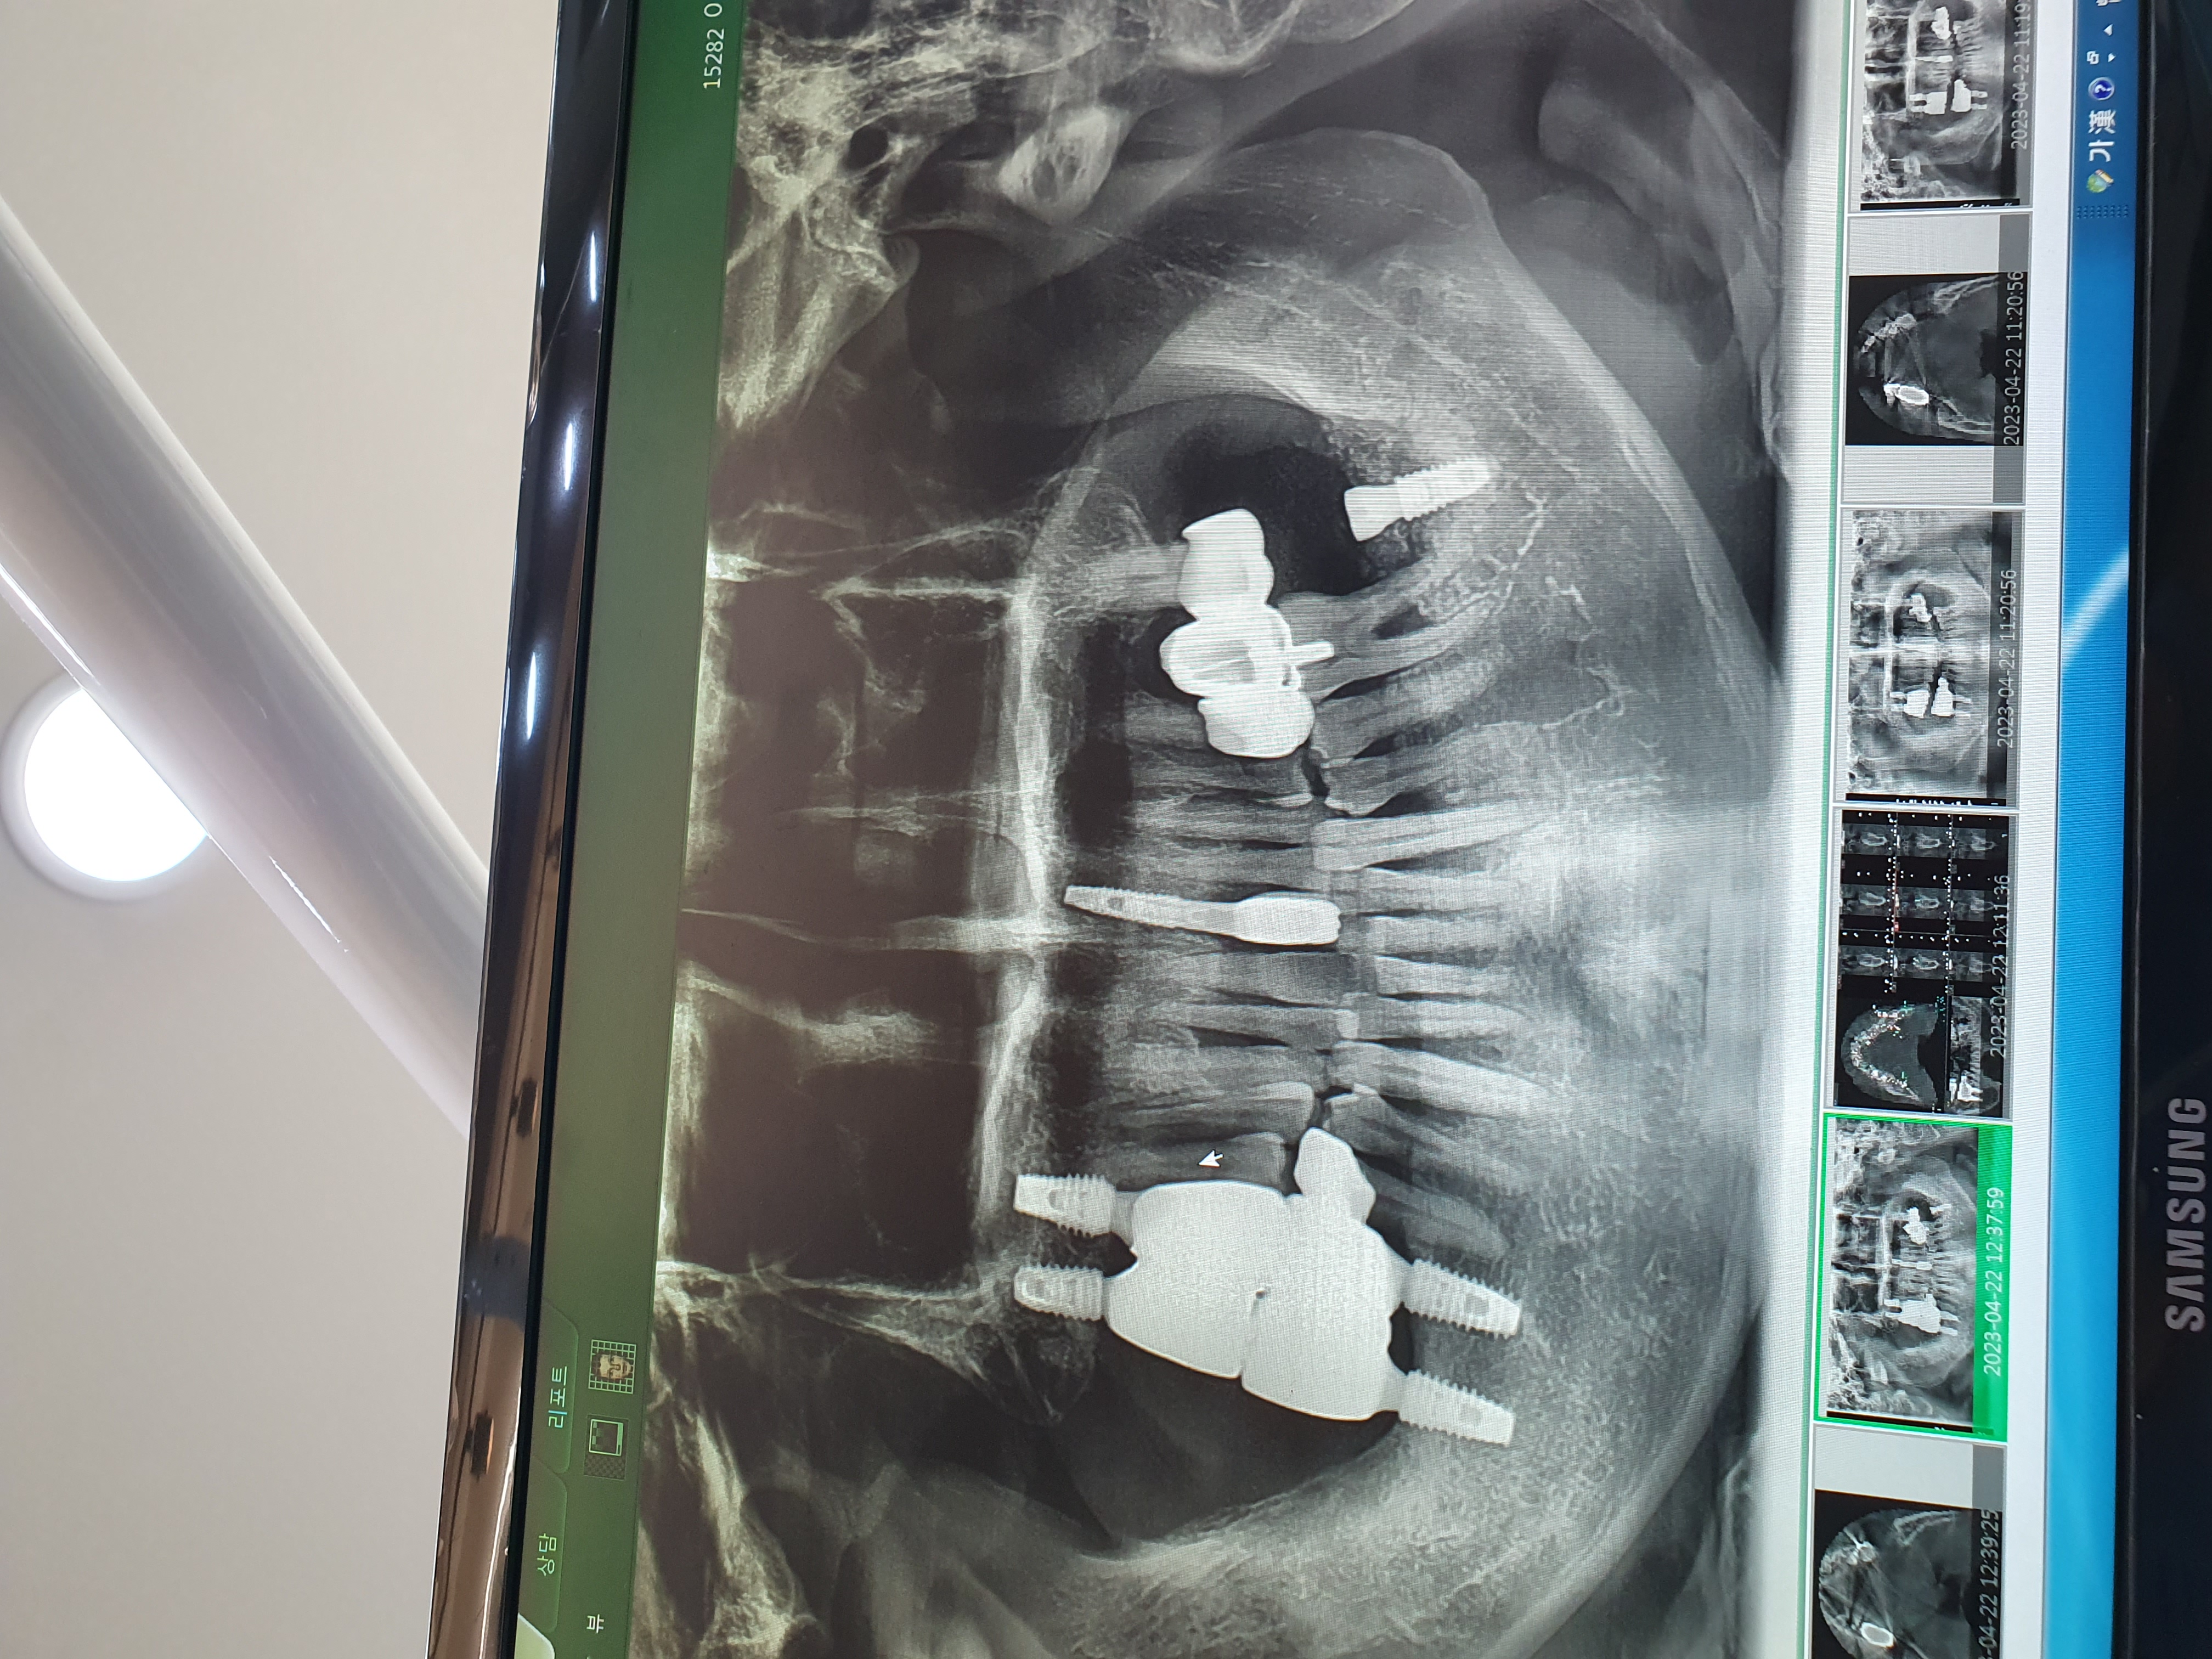

전

후

경기도 화성에 거주중인 48세 남성입니다. 캐시닥을 통해 다비드치과를 알게 되었습니다. 간단한 전화 상담 후 내원하여 검진 후 임플란트 시술을 결정하였고 당일 동네 병원보다 거의 40%저렴한 가격에 뼈이식과 7개 임플란트 식립까지 마쳤습니다.